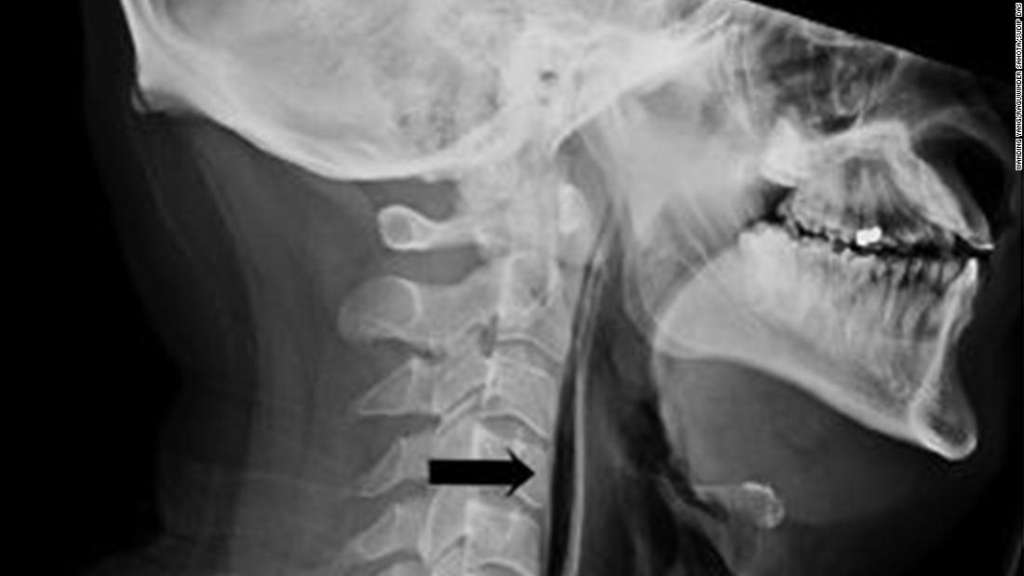

Initially, doctors saw swelling in his neck and when they examined the soft tissue they heard popping and crackling. Yang said that meant there were air bubbles getting into the man’s muscles and deep into his tissue.

Scans confirmed the problem. The tests showed actual streaks of air in the retropharyngeal region and extensive surgical emphysema in the neck anterior to the trachea. In other words, by trying to hold in his sneeze, he actually blew a small hole in his throat.